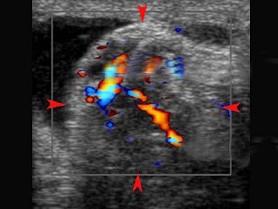

问题 根据超声图像,最可能的诊断为 ?(?)

选项 A.附睾炎 B.睾丸扭转 C.卵巢囊肿蒂扭转 D.子宫腺肌瘤 E.以上都不是

答案 A